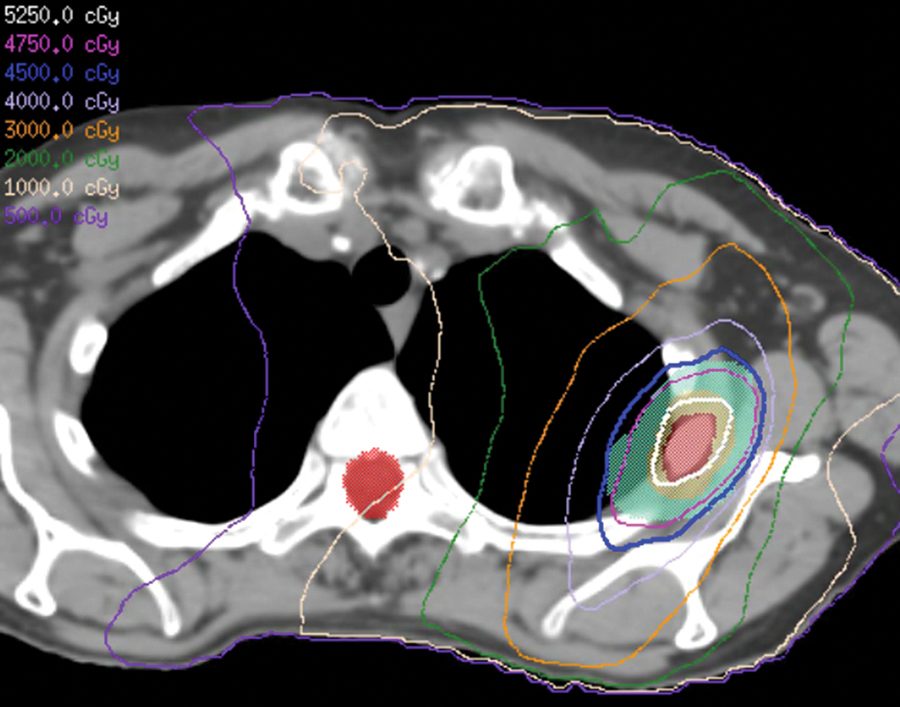

Terapia local consolidativa más inmunoterapia o agentes dirigidos para el NSCLC

Ensayos clínicos exploran la cirugía/radiación más un régimen de inhibidores de puntos de control inmunitario o de la tirosina cinasa para el cáncer de pulmón no microcítico metastásico